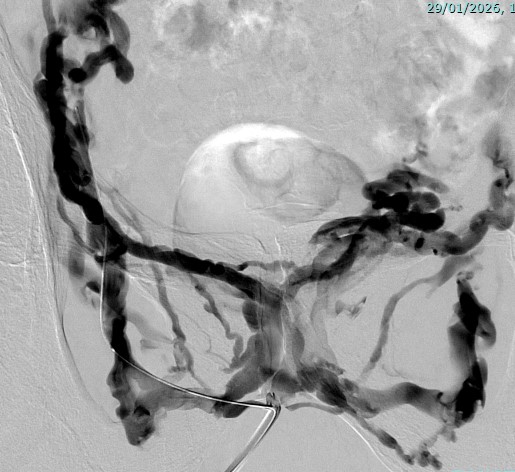

Angiographie :

Une imagerie des vaisseaux sanguins est réalisée pour localiser les rétrécissements ou la fuite sanguine.

En cas de fuite veineuse :

Embolisation de celle-ci : de la colle biologique est injectée pour boucher la fuite.